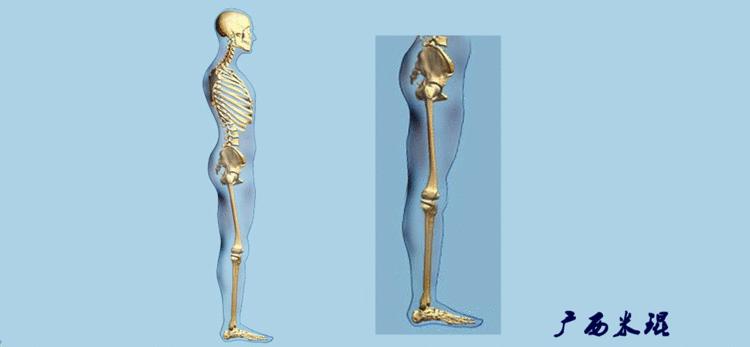

机械轴要分前后位及侧位,站立前后位(也就是冠状面)股骨头中心与踝关节中心的连线通过膝关节中心,这是下肢的机械轴线,也就是下肢力线,常说Mikulicz线。冠状面的力线评估在临床工作中最常用、最基础、最重要。

站立侧位(矢状面)股骨头中心与踝关节中心的连线也通过膝关节中心,这也是下肢的机械轴线,这也是下肢力线。

矢状面的下肢力线常常被医生忽视,其实它的改变也是膝关节疼痛的常见原因。

(3)垂直轴

也就是下肢的负重轴,它是身体的纵轴线,与地面垂直,由于双髋比双踝的距离宽,所以垂直轴与下肢力线(机械轴)存在3°的外翻。

开始接触时可能我们对这些轴有点混乱,通过下面的这张图片就能清楚的了解下肢几个轴之间的关系。